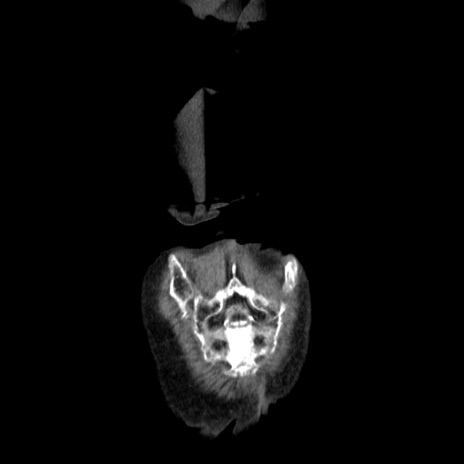

症例25(冠状断像)